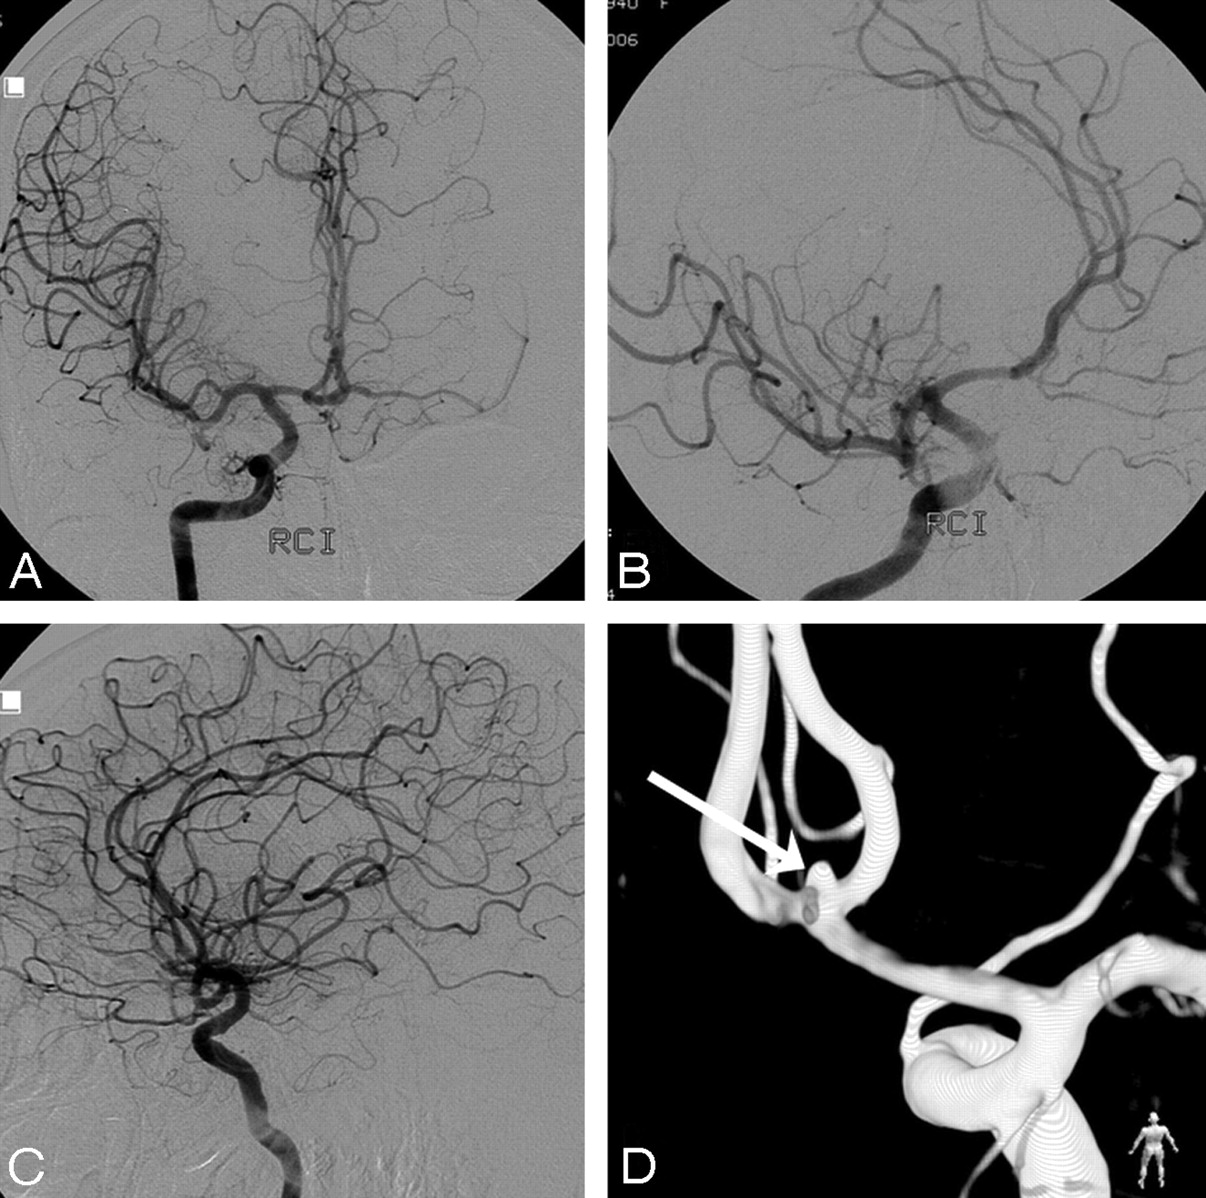

A 67-year-old woman admitted with grade IV SAH, comatose and ventilated. CT scan showed diffuse subarachnoid blood. A–C, Right internal carotid artery angiogram in 3 projections fails to demonstrate an aneurysm. Note filling of both A2s and A1s. D, Posterior view of 3DRA depicts a 1.6-mm anterior communicating artery aneurysm (arrow). This aneurysm was clipped 1 week later.

These figures, in combination with other studies that assessed the additional value of 3DRA in the general detection of aneurysms,12-14 indicate that 3DRA probably depicts more DSA-occult ruptured aneurysms than repeat DSA only. Another advantage of using 3DRA as an additional imaging technique in patients with angiographically negative SAH is the possibility of a 3D acquisition in the same session as the first DSA in selected cooperative patients, thus obviating a second angiographic procedure. If a DSA-occult aneurysm is detected, therapy can be immediately instigated, and the risk of recurrent hemorrhage is reduced. In uncooperative patients, a second procedure cannot always be avoided because additional 3DRA requires general anesthesia or deep sedation to ensure no patient motion during the acquisition of the 8-second rotational run. In most cases, the acquisition of 3DRA can be limited to 1 or 2 vessels, depending on the distribution of subarachnoid blood on CT. For example, when a maximal amount of blood is present in a Sylvian fissure, 3DRA of the ipsilateral carotid artery is sufficient to confirm or exclude a middle cerebral artery aneurysm (Fig 2). When blood is evenly distributed in the basal cisterns, this may be indicative of an anterior communicating artery aneurysm, and 3DRA may be restricted to the 1 carotid artery filling both A2s, as is apparent on DSA (Fig 3). For the most part, 3DRA of 3 or even 4 vessels is needed only in cases in which no aneurysm will be found.